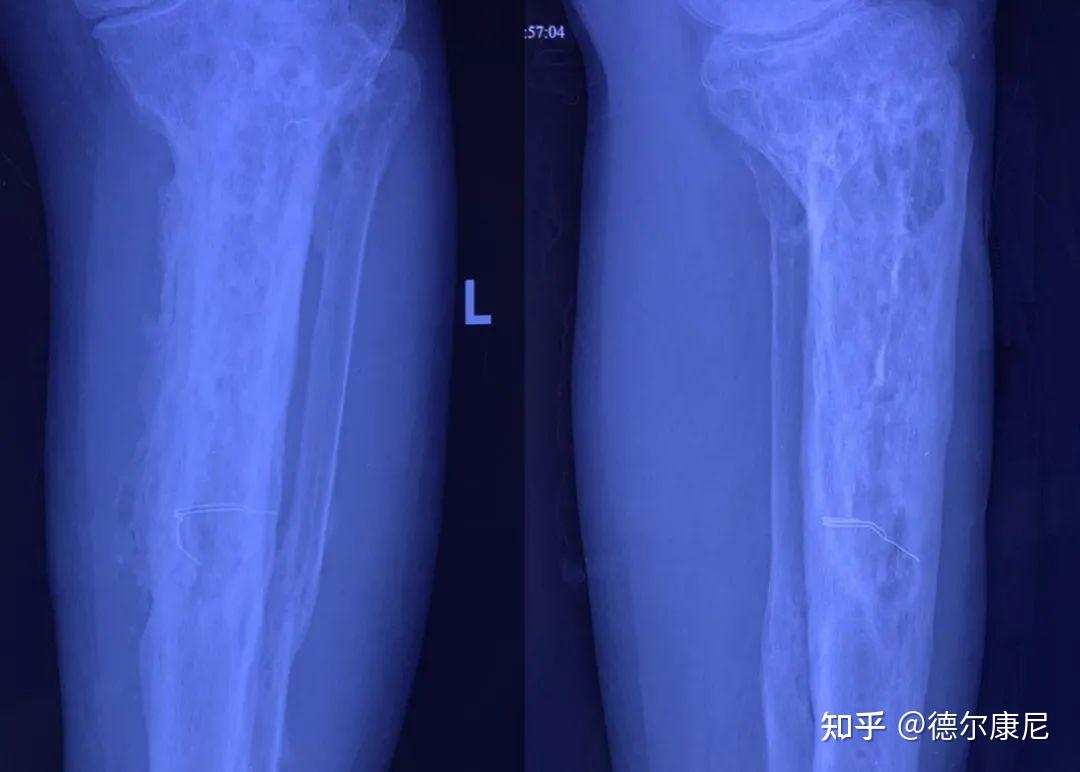

慢性骨髓炎两个月,骨缺损,美容科用骨水泥填充错误!

图片尺寸2000x3556